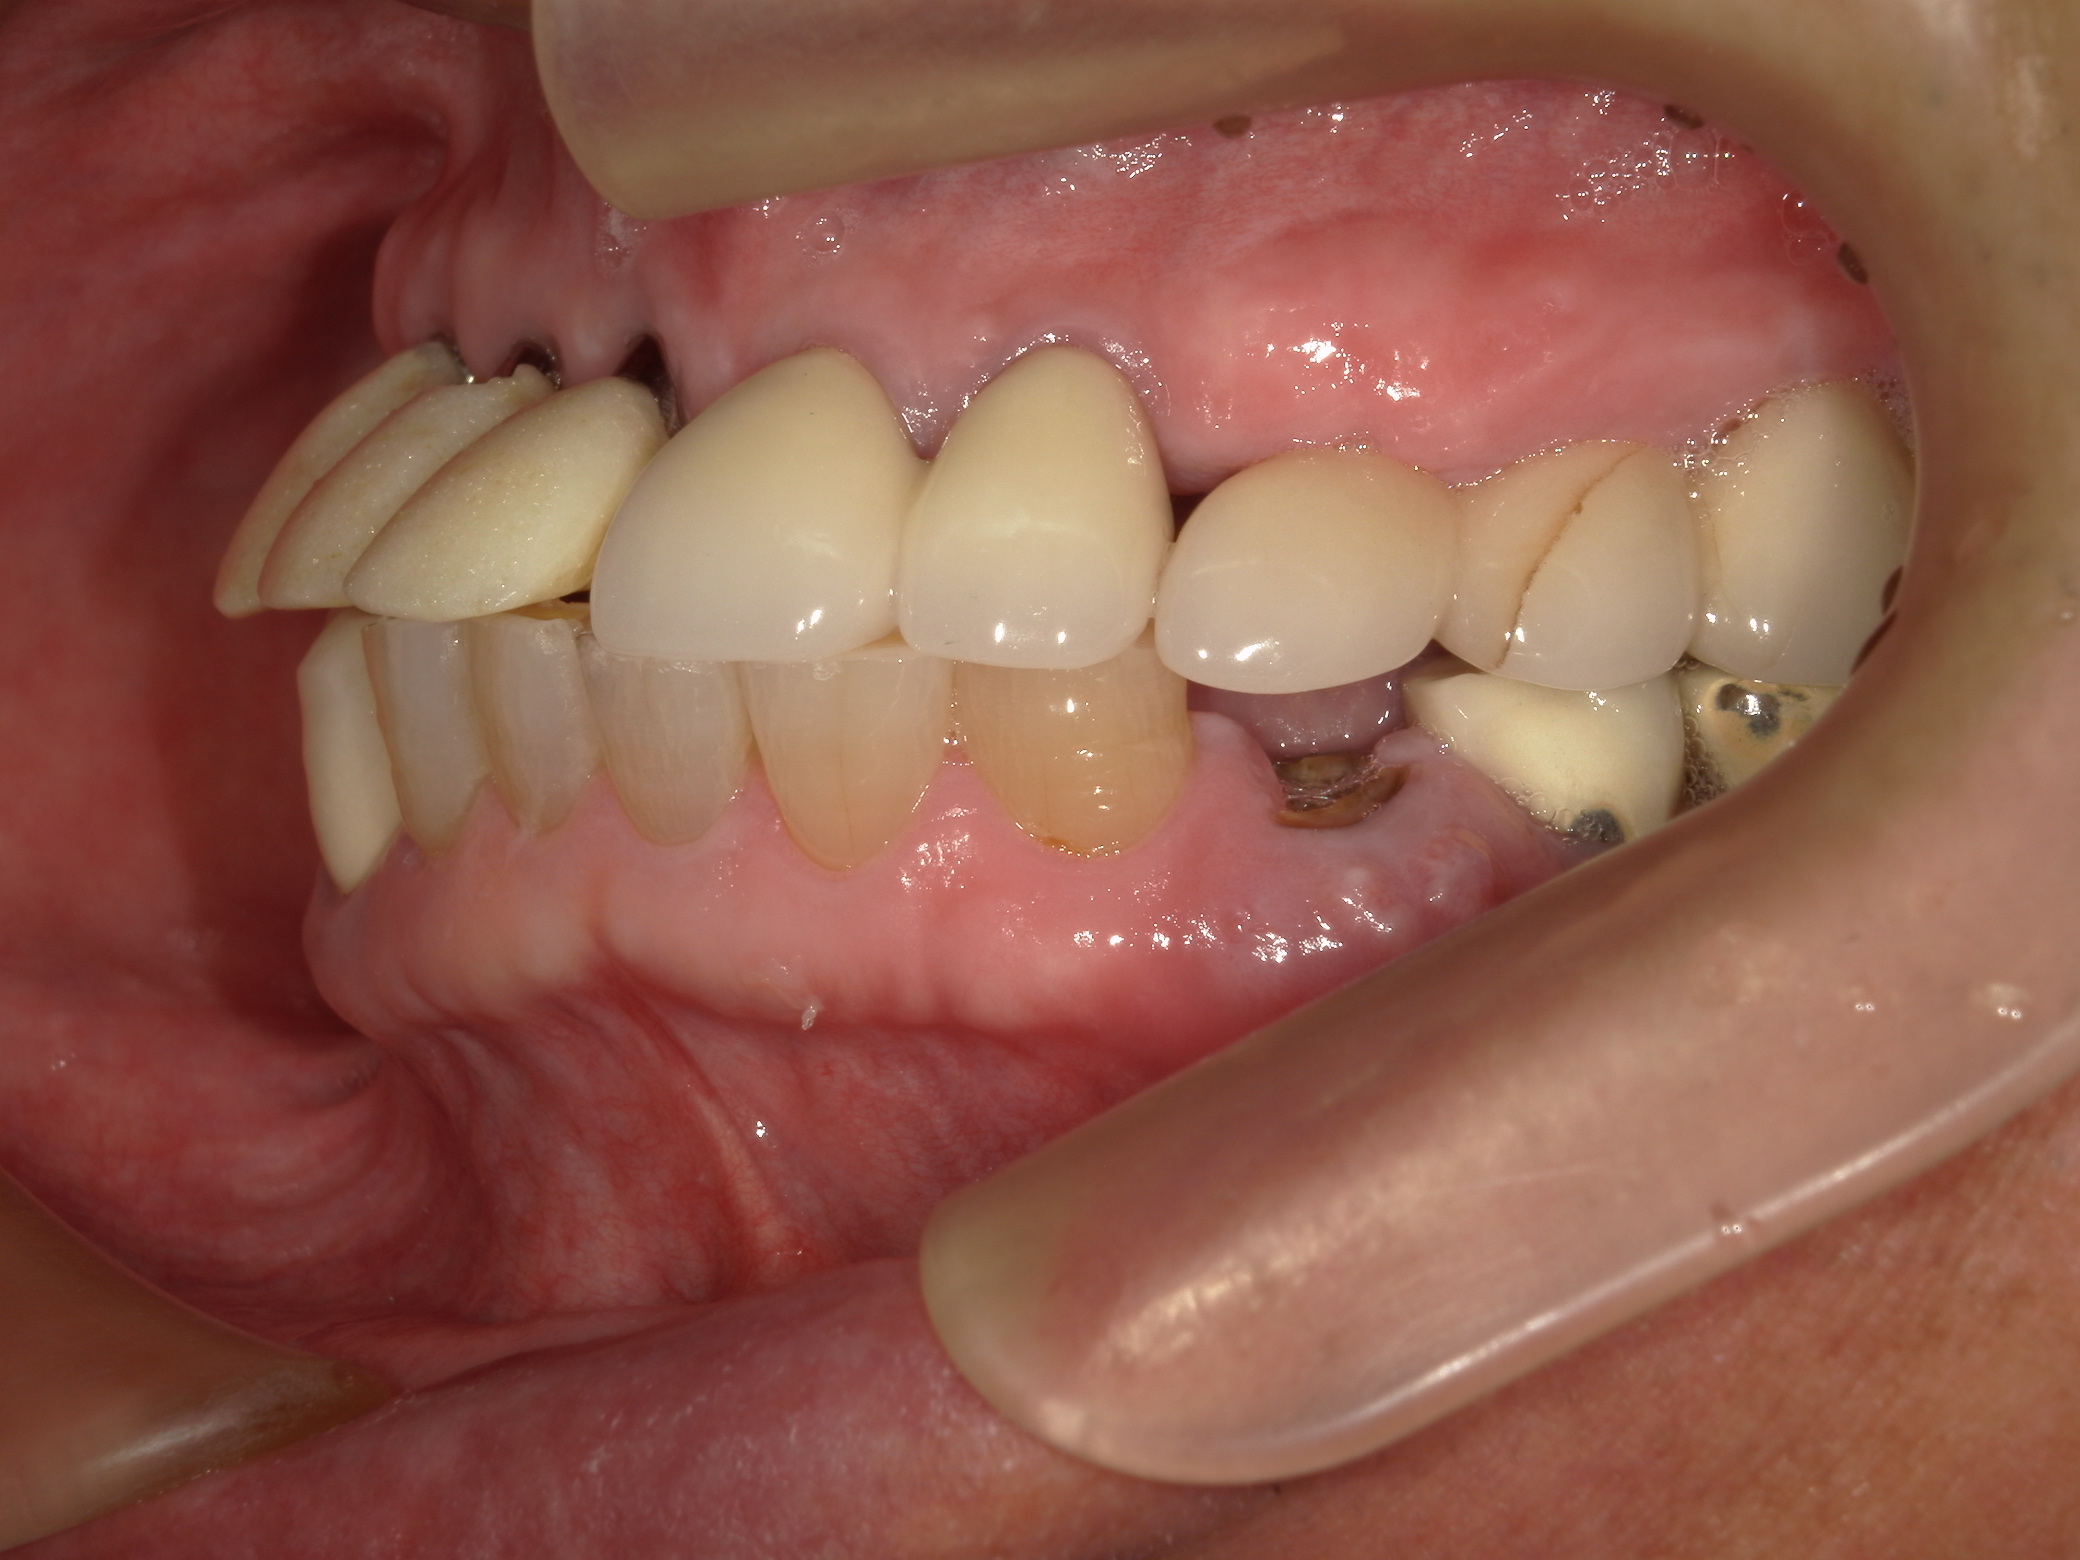

右側面です。横から見ると問題がはっきりします。上顎前歯の歯軸傾斜が強すぎます。右上5番から左上7番までがインプラントです。右上4,5は仮歯が壊れて外れた、と言っていました。上顎前歯はかなり無理な補綴がしてあります。すごい出っ歯ですね。セファロ分析はしていないので正確さに欠けますが、おそらく骨格性の反対咬合であったと思われます。

左側面です。左下4番は残根状態で抜歯が必要でした。